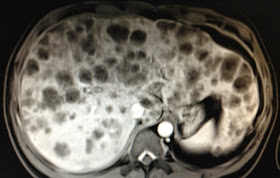

MRI  with

gado CE detected  also  many

round  spots,   same size of  2

cm, with central necrosis looked like metastasis.